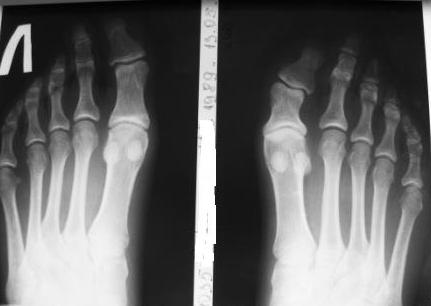

Рентгенограммы прилагаю.